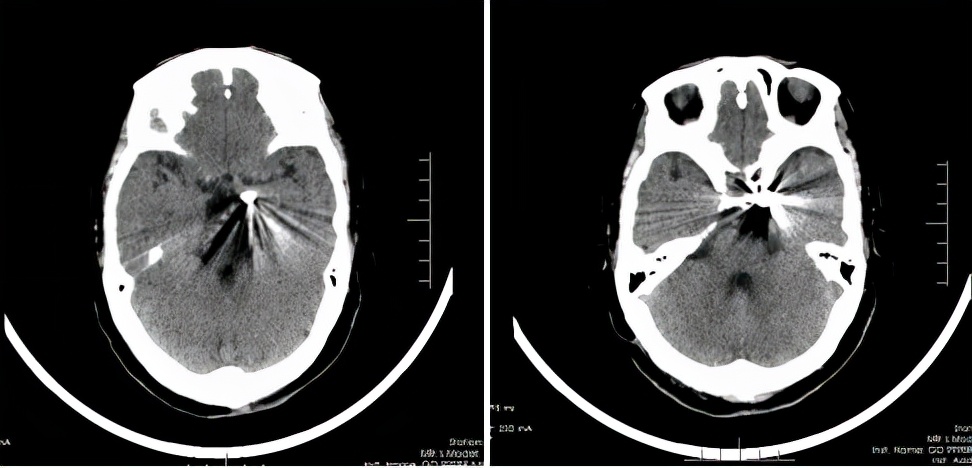

术后复查

颅内动脉瘤是颅内动脉壁上的异常膨出,该病可发生于任何年龄,是一种致残致死率较高的脑血管疾病。对此类病人,应当明确诊断、及时治疗,才能获得满意效果。颅内动脉瘤的主要临床症状有反复的头晕、头痛,由于患者常伴有高血压病史,严重时会使薄弱的动脉壁发生破裂,进而形成脑出血。“本案例中,由于患者左侧后交通动脉瘤体积比较大,导致患者出现头晕、头痛、动眼神经麻痹、眼睑下垂等症状,任由其发展下去可能会引起生命危险。”金鑫介绍,动脉瘤一旦破裂,第一次出血的死亡率达40%,第二次出血的死亡率为60%~70%。因此,他提醒,一旦发现脑动脉瘤,要早密切随诊,防止延误病情。